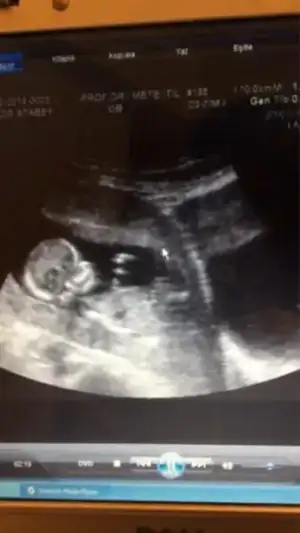

dr soylemeden siz gorun genital nub teorisi ( bebegin cinsiyeti)

$ImageUploadedByKadınlar Kulübü1398251579.717078.webp $ImageUploadedByKadınlar Kulübü1398251598.562961.webp

kizlar merhaba benim bebiş 12+4 cinsiyeti hakkinda yorum yaparmisiniz

evet canim popo bölgesi direk orayi fotograf cektim zaten erkek diyorsun yani cokmu belli oluyor erkek oldugu 17.haftalik burda tesekkür ederim hayirlisi olsun insallah allah sagsaglim herkesin kalbine göre versin :emir_bebek::nazar:

cnm doktor soylemedimi cinsiyetini bu teoriyegore erkek ama allah gonlune gore versin